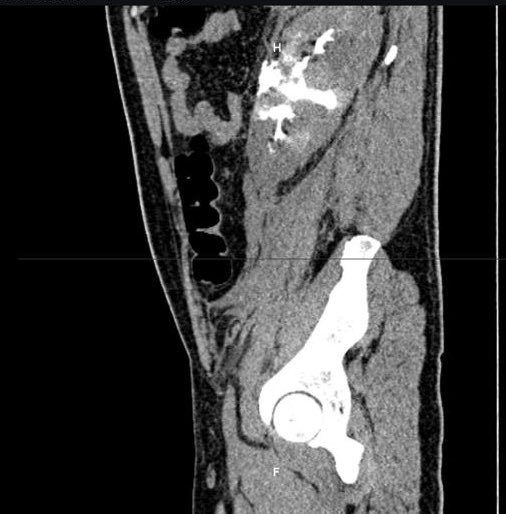

@AqcQuiroz @omarvic18 @nallelyjjg CT rendering and radiomica análysis for testicular cancer #radiomic #testicularcancer #UroSoMe #uroncology